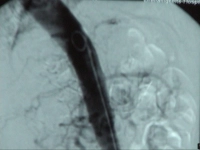

Video clip: SMA occlusion close to its origin with occlusion of the celiac trunk